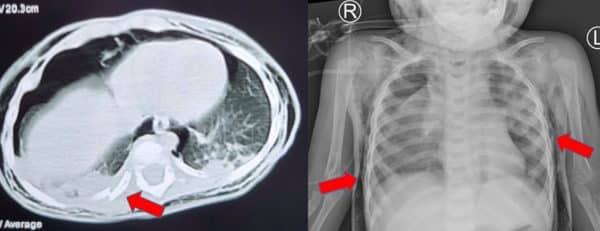

Tại bệnh viện, bác sĩ ghi nhận bệnh nhi lừ đừ, môi tím, khó thở, SpO2 85% và được đặt nội khí quản, thở máy, chụp CT-Scan đầu – ngực – bụng. Kết quả chụp cho thấy bệnh nhi bị tràn khí dưới da vùng bụng, hông, lưng, ngực, cổ hai bên, xẹp thùy trên phổi hai bên và thùy giữa phổi phải, vỡ khí quản, tràn khí trung thất, gãy xương sườn 8, 9, 10…

Bé P. được chuyển đến Bệnh viện Nhi đồng thành phố và được hội chẩn các chuyên khoa hô hấp, tai mũi họng, hồi sức ngoại, gây mê hồi sức chẩn đoán: vỡ khí quản, gãy xương sườn 8, 9, 10 (phải). Các bác sĩ thống nhất xử trí mở ngực phẫu thuật tạo hình khí quản, nội soi phế quản kết hợp khi mổ.